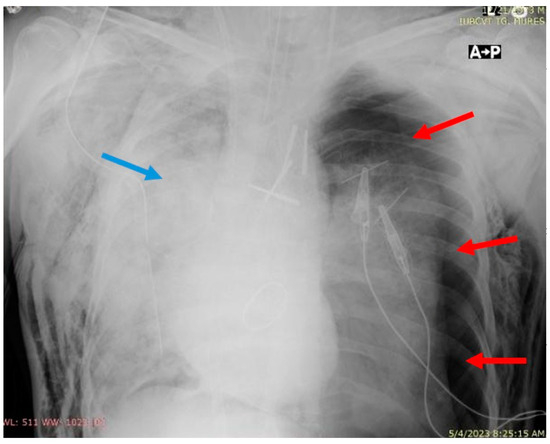

| Postoperative evolution | Right after Intensive Care Unit (ICU) admission, hypoxia abruptly developed, and serous discharge was aspirated through the endotracheal tube. The thoracic X-ray performed revealed dense alveolar opacities on the entire right hemithorax, confirming the diagnosis of unilateral pulmonary edema. | |

| The patient developed hemodynamic instability requiring cardiopulmonary resuscitation. Peripheral VA-ECMO support was instituted during resuscitation, with the cannulation of the right femoral artery and vein, improving hemodynamic and respiratory parameters. | ||

| Day 1 | The patient developed a left pneumothorax, confirmed by thoracic X-ray, worsening respiratory parameters, therefore requiring the insertion of a drainage tube. A thoracic X-ray after drainage confirmed the correct positioning of the tube and the complete expansion of the left lung. | |